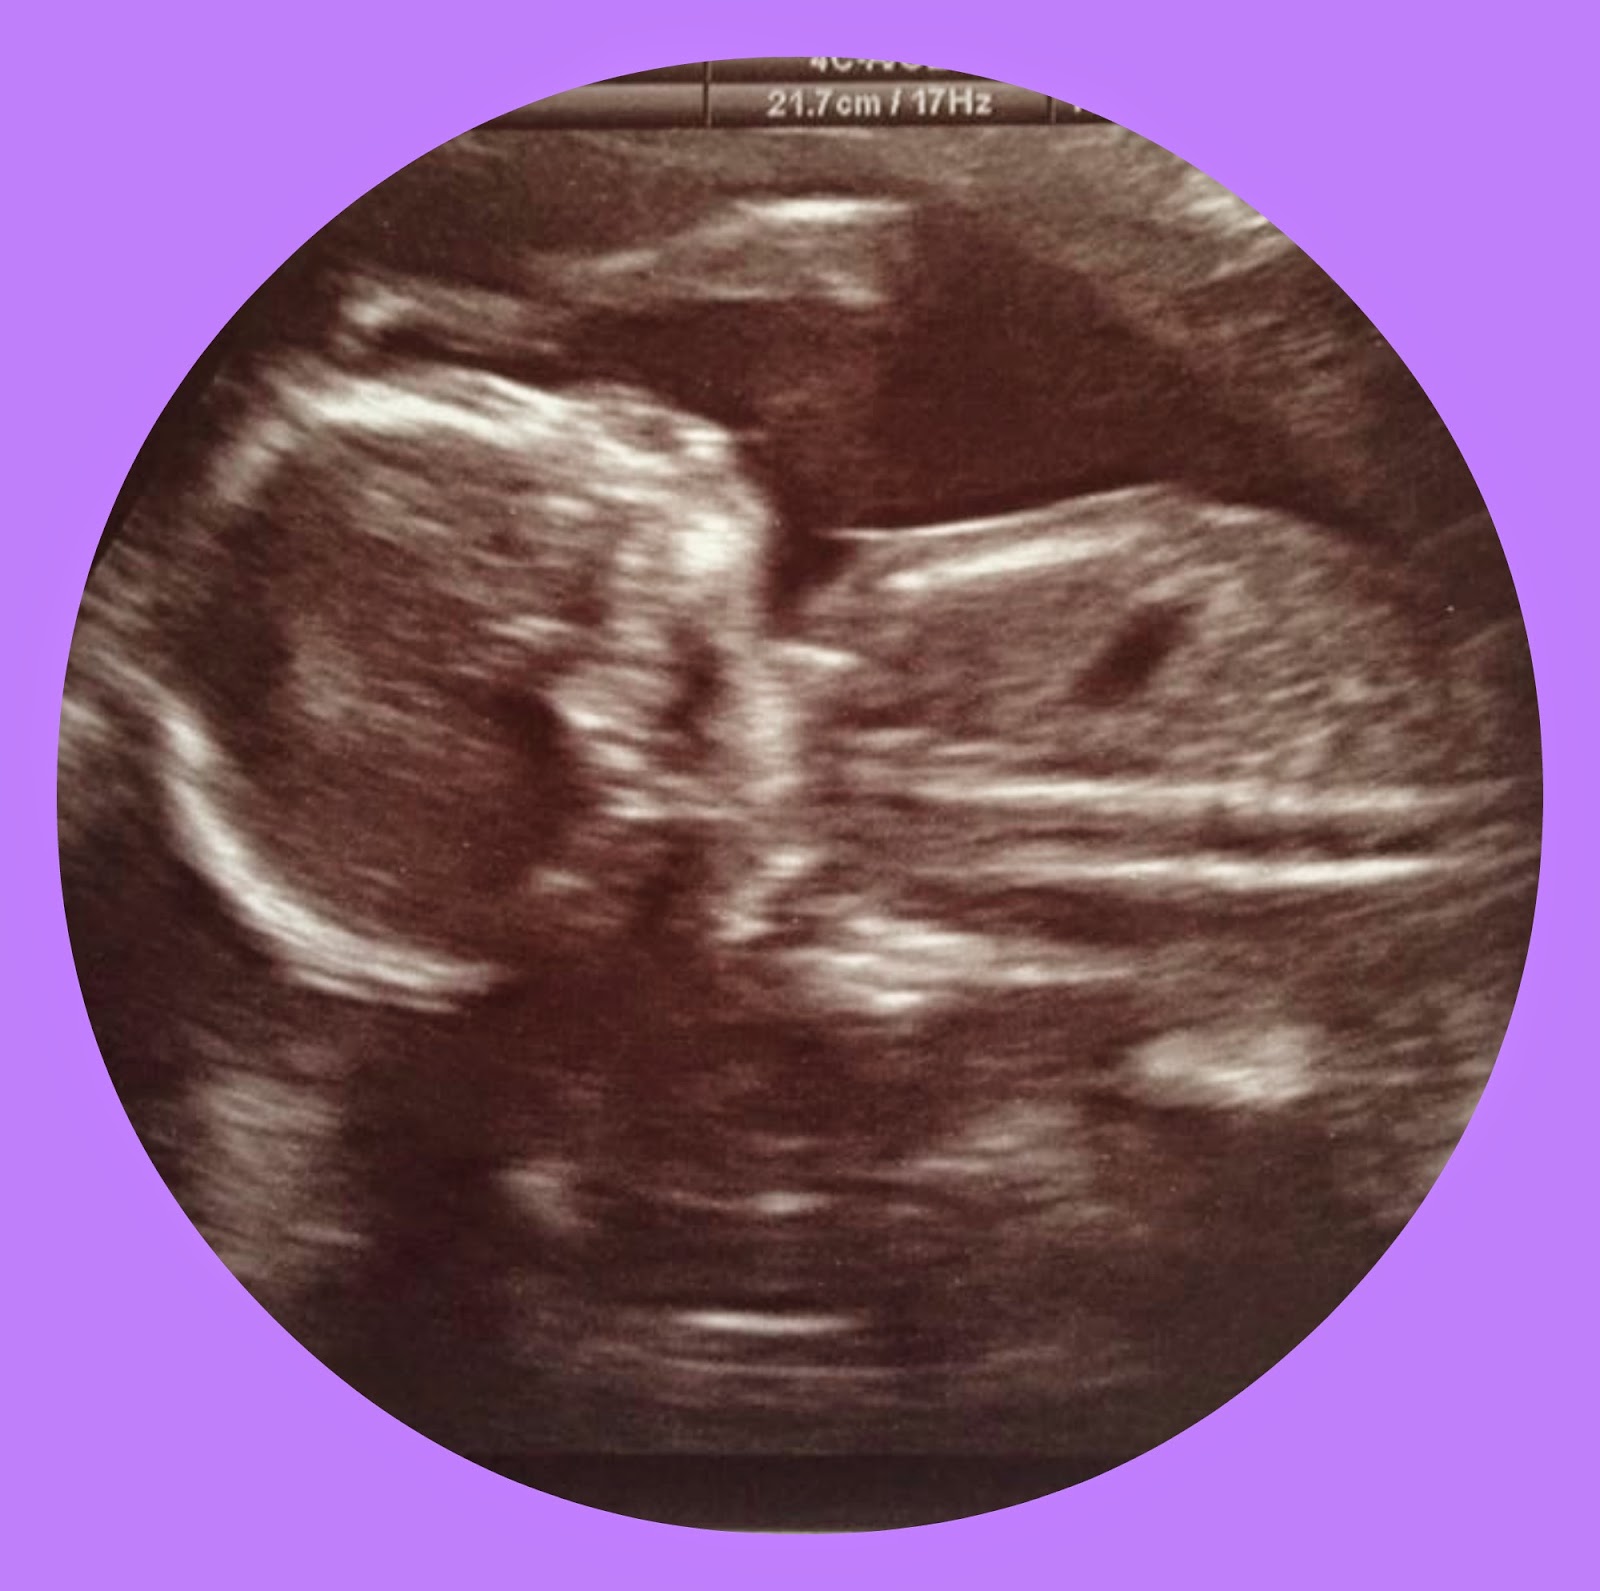

Last week we had our our abdomaly scan, although a lot of parents think that this scan is to determine the babies gender which of course you can at this stage but its your decision whether to find out the sex of the baby or to have a surprise, as much as I love surprises I have found out with all my pregnancies what the sex of the baby has been, just for planning and I personally couldn't wait.

However as I said above this scan isn't to find out the gender, its mainly to measure all of babies vitals/major organs for example the brain, heart, skin, spine check that baby isn't going to have a cleft pallet the scan takes around twenty minutes to half an hour - or should do as long as baby is in the right position.

I had my scan and baby, really did not want to play ball at all, every time the sonographer tried to measure anything the baby moved or turned the wrong way or was hiding so after about twenty minutes of being poked and prodded, she sent me off to go for a walk a fizzy drink to see if baby would move positions. When I went back baby had moved positions but into a worse position and baby also it had its legs crossed, I was told I would have to come back in a few days time - naturally this worried me I have never known it although the lady did reassure me this happens quite often and there was nothing to worry about, of course I still did worry I didn't sleep very much over the next few nights.

After the few days had passed I trundled off for the second of my two twenty week scans hoping and preying everything was going to be alright, it seemed like a lifetime until they called my name, going in I watched the screen closely as this time baby was in a better position, the lady who was performing the scan remained somewhat silent throughout whilst she measured each little bit of baby, she then stopped to ask me if I wanted to know the sex of the little one, I nodded she said its a boy she showed me what was supposedly his boy bits although it wasn't obvious baby was a boy well not to me anyway, but it is another little boy.

The scan seemed to be over pretty quickly after that with the relief that everything is where it should be and baby is alright thank goodness!